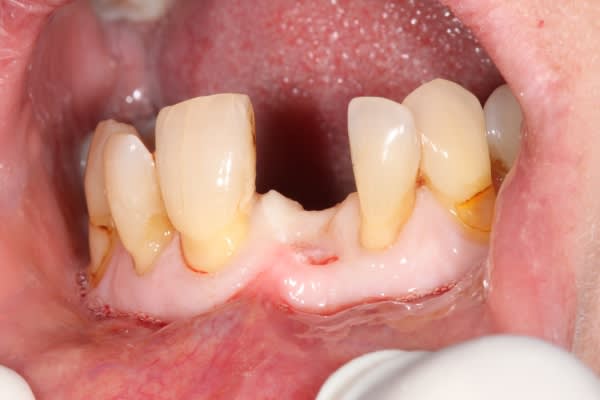

Un cas qui ressemble mais avec un implant qui n'est pas à l'intérieur du boitier osseux mais reconstitution de la paroi vestibulaire après pose d'un implant sur crête mince avec expansion, fissuration de la corticale vestibulaire.

Effondrement tissulaire après extraction et lambeau repositionné coronairement pour essayer de retrouver une papille entre centrale et latérale. La dent de la patiente est recollée.

La technique est bonne pour moi parce que les résultats sont constants en terme de reconstruction horizontale mais pas en verticale.

j'ai un cas similaire qui cicatrise et puisque que l'on parlait de recouvrement gingival, voilà un cas où j'espère un résultat sympa... en tout cas c'est prometteur

1 et 2 pré op

3 6 semaines après extraction

4,5,6 intervention avec pilier et barre titane

7 3 semaines post chir à la dépose des points